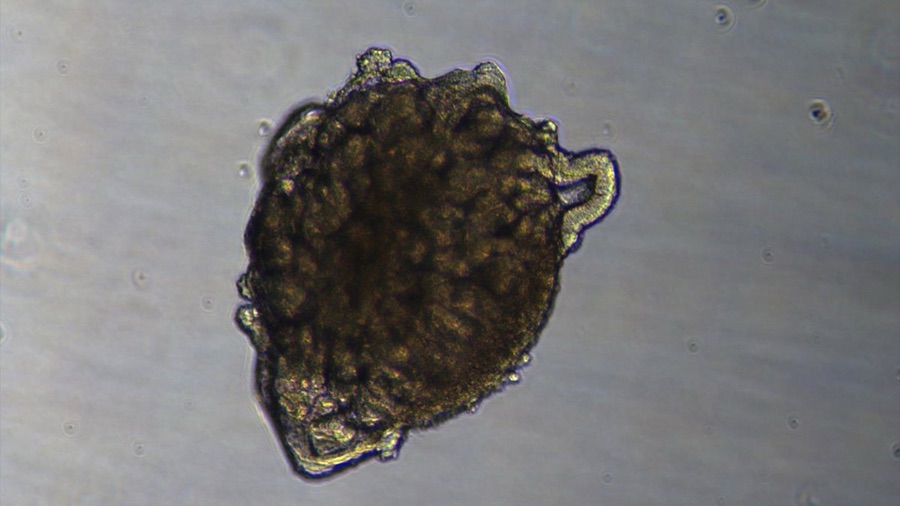

Un organoide de riñón es una estructura tridimensional, de unas micras de tamaño, cultivada en el laboratorio a partir de células madre humanas y, aunque no es un órgano completo, «reproduce muchas de sus estructuras y funciones principales» y permite estudiar cómo se desarrolla el riñón.

El nuevo método permite generar miles de organoides renales en condiciones controladas y en poco tiempo, con una gran precisión y sin necesidad de componentes complejos, lo que «abre la puerta a aplicaciones como la detección de fármacos o el estudio de enfermedades».